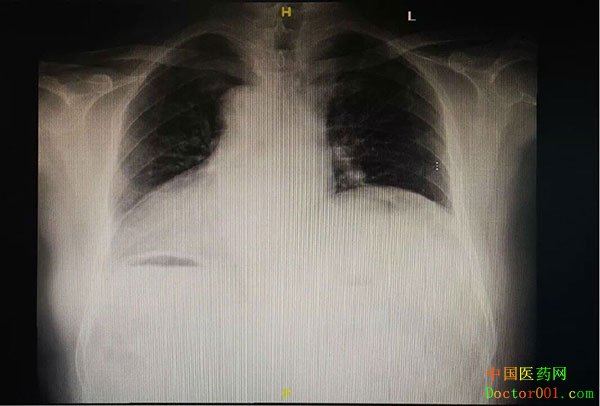

会诊时听说患者是“右位心”,当时只是觉得好奇,真正当姜大爷转了科,才让包括谭主任在内的全科人“大开眼界”。 按照正常流程进行心电图检查,却做出“反向图像”,做身体检查时用听诊器,但“心音听不到”! 原来,和正常人心脏在左边相反,姜大爷的心脏长在了右边,而且属于“右位心”中的“镜面右位心”,即除了心脏,肝脏、肺脏、脾脏等胸腔内其他脏器位置也发生了“乾坤大挪移”,恰如正常人身体脏器位置在镜中的映像。 医学资料显示,“右位心”在自然人中发生率约为万分之一~二,公开报道这类患者进行心脏介入治疗的案例也是少之又少。姜大爷该如何进一步治疗呢? 防血栓是重中之重 自己具体有多少年的房颤病史不清楚,但肯定十几年前就被确诊过,姜大爷因没有任何房颤症状,一直没当回事儿,也从来不知道房颤会导致血栓栓塞,需要长期吃抗凝药物。 临床上像姜大爷一样的患者非常多,房颤抗凝这个老生常谈的问题,再次让谭主任忧心忡忡:房颤没有症状,不等于不会诱发血栓!这次姜大爷不幸中的万幸是栓塞发生在上肢,且及时就医,如果是脑梗塞,后果将不堪设想。 针对患者的情况,谭主任和患者沟通:要么终生服用抗凝血药,要么用左心耳封堵术这种微创手术,闭合血栓发源地—左心耳(大约90%的栓子来源于左心耳)来降低房颤中风的风险。最终患者和家属选择了做左心耳封堵手术。 一场“逆式而为”的左心耳封堵术

自从决定实施左心耳封堵术,谭主任立即启动MDT会诊机制,邀请北京朝阳医院刘兴鹏、四川省人民医院曾杰、浙江大学医学院附属邵逸夫医院蒋晨阳、北京朝阳医院超声科吕秀章教授等多位不同亚专科的专家组成会诊小组,实时商讨姜大爷的手术方案。 术前心脏CTA显示,姜大爷虽为“镜面右位心”,其左心耳解剖形态相对较好,符合左心耳封堵手术要求。但毕竟患者身体构造特殊,除了周密、详细的手术方案,谭主任还邀请心外科医生待命,如果术中出现特殊情况,利用外科手段进行心耳夹闭。 尽管都是超级熟手,整个手术团队仍然是“小心翼翼”。因为虽然手术操作流程一样,但一切全部得反着来:穿刺左侧股静脉-左侧位房间隔穿刺-左心耳造影-放置封堵器……不管是术中全程引导食道超声的吕教授,还是手术操作的曾教授和谭主任等术者,大脑中时时要绷着一根弦。 “所有的手术习惯、手术走向都是反着的,我们只能把思维、手法翻转180度来进行。简直和以往训练了20年的医学习惯完全相反,一度我们都觉得自己突然变笨了,就像大陆司机突然到了香港开车,特别考验思维和心理。”曾杰教授说。 最终,2019年8月2日,国内首例“镜面右位心”的左心耳封堵手术在河北燕达医院心内二科顺利完成。在超声监测下,可以看到封堵器的伞形封堵装置准确地植入了患者的左心耳,各项指标完全符合此项手术业内公认的“PASS”成功标准原则,而这种微创介入手术,耗时只有一个多小时。 出院前,在征得姜大爷及家属的同意后,我们用视频记录下了姜大爷对此次燕达就医的真实感受。希望此次成功的左心耳封堵手术,能为这位“万里挑一”患者的心脏健康撑起一把保护“伞”……. 河北燕达医院心血管内二科专家实力雄厚,技术突出,专家涵盖心脏疾病各个亚专业,心律失常、心力衰竭等诊疗领域。科室采取“1+N”合作模式,采取常态化多学科专家组协作诊疗(MDT)和连续完整闭环患者管理模式,致力于为广大心脏疾病患者提供个体化疾病解决方案和更优质的医疗服务。